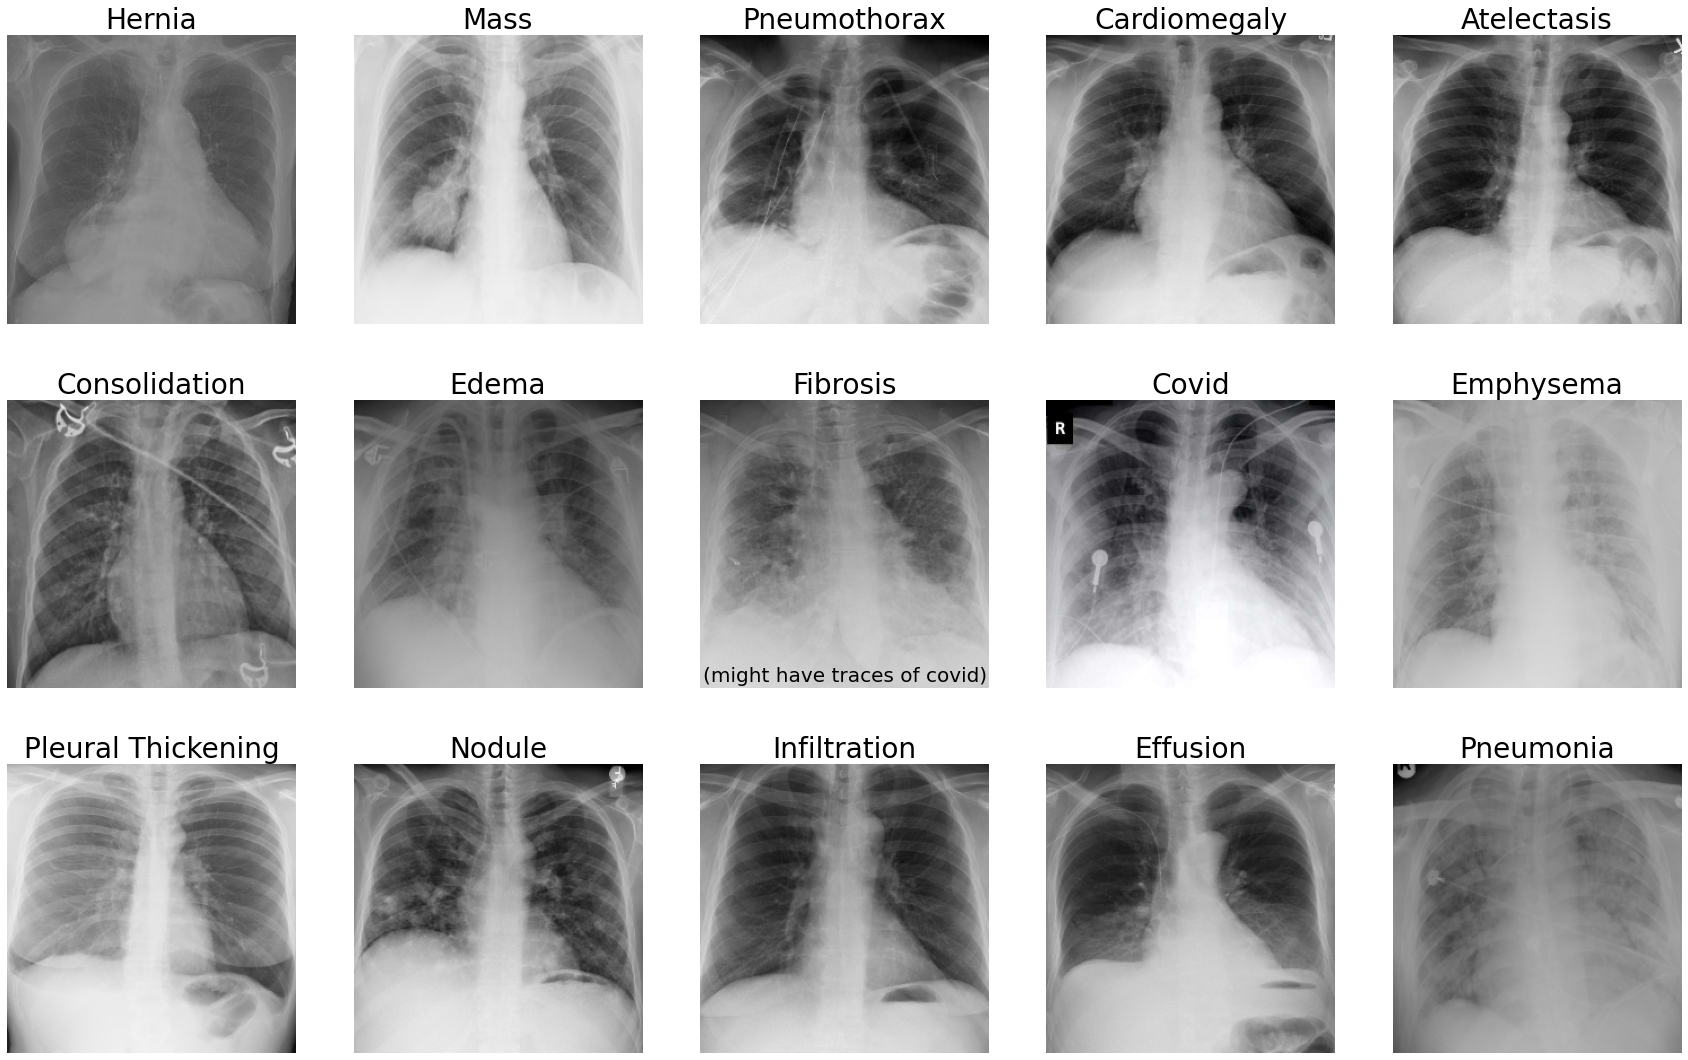

In Fig. 5, as illustrations, we display one example each of the 15 classes which is correctly classified by the system.

Figure 5: Examples of correct classification including COVID-19